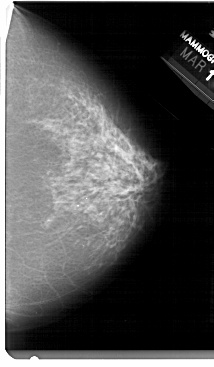

A_1480_1.LEFT_CC

LEFT_CC LINES 5491 PIXELS_PER_LINE 3001 BITS_PER_PIXEL 12 RESOLUTION 43.5 OVERLAY

FILE: A_1480_1.LEFT_CC.OVERLAY

TOTAL_ABNORMALITIES 1

ABNORMALITY 1

LESION_TYPE CALCIFICATION TYPE PLEOMORPHIC DISTRIBUTION CLUSTERED

ASSESSMENT 4

SUBTLETY 1

PATHOLOGY BENIGN

TOTAL_OUTLINES 1

BOUNDARY